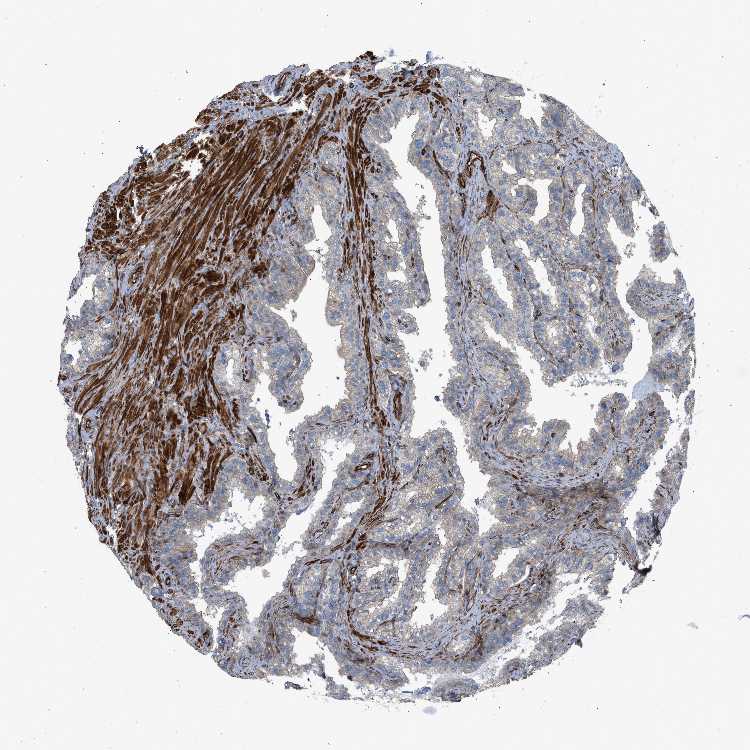

SEMINAL VESICLE - Antibody stainingi

Antibody staining in the annotated cell types in the current human tissue is reported as not detected, low, medium, or high, based on conventional immunohistochemistry profiling in selected tissues. This score is based on the combination of the staining intensity and fraction of stained cells.

Each image is clickable and will lead to virtual microscopy that enables deeper exploration of all samples and also displays staining intensity scores, fraction scores and subcellular localization as well as patient and tissue information for each sample.

Antibody HPA015870Antibody HPA021872

Glandular cells LowNot detected